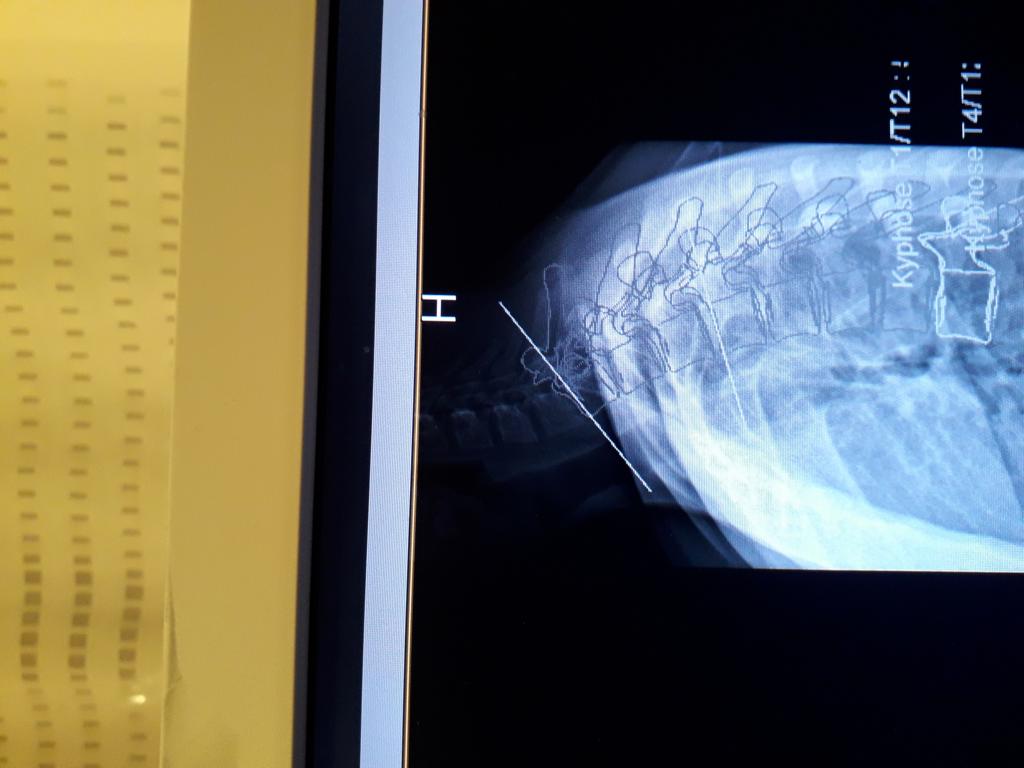

Ich hoffe mal das angehängte Bild ist halbwegs erkennbar, sonst werde ich es noch einmal versuchen. Die im ersten Beitrag genannten BWS-Werte sind komischerweise auch in dem Originaldateibild selbst am Rand nicht sichtbar, ergeben sich aber aus anderen Bilddateien.

Wirbelsäulenseitaufnahme.JPG

(102.63 KiB) Noch nie heruntergeladen

der obere BWS Bereich ist nicht so gut zu sehen bzw. es fehlt das Stück bis zur HWS einschliesslich!

Versuche ich von unten zu zählen, komme ich vielleicht zum T6 (??) als Scheitel der Kyphose, was normal wäre.

Es wird eigentlich auch ein Gesamtwinkel angegeben und irgendwie habe ich den optischen Eindruck, dass Deine BWS eher abgeflacht sein könnte, was widerum für die Übung Hocker über dem Kopf "nach innen zusammendrücken" bei Flachrücken spricht. Trotzdem "zur Hälfte" bzw. stärker gegen eine Hyperkyphose vorzugehen, stellt mich vor Rätsel.

Insofern ist es schwierig, Tipps zu geben, wenn die Diagnose nicht eindeutig ist.